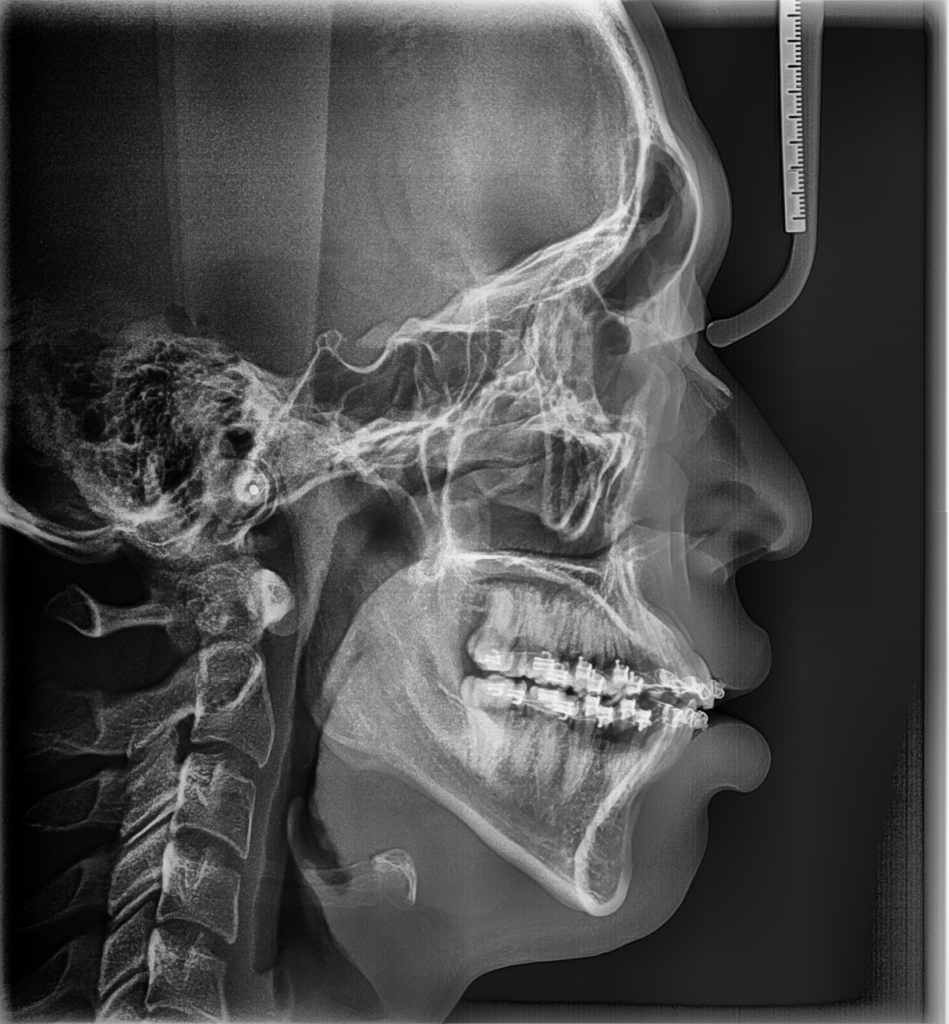

두번째 사진은 비발치 교정 시작하고 2년 지난 시점입니다(이후에 바로 발치교정으로 돌아섰습니다)

• 2번 째 사진